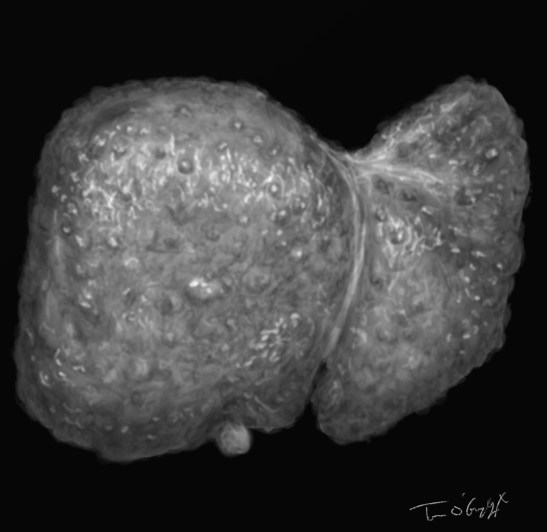

Le volume du foie est finalement variable au décours de la maladie, on peut percevoir une hépatomégalie à la palpation, dure, bosselée en cas de cirrhose macronodulaire. Mais elle devient difficile parfois dans les volumineuses ascites, et on peut aussi voir une atrophie du foie dans les évolutions terminales.

Cirrhose hépatique secondaire à une hépatite B chronique, splénomégalie volumineuse, scanner correspondant à l’échographie sus-jacente